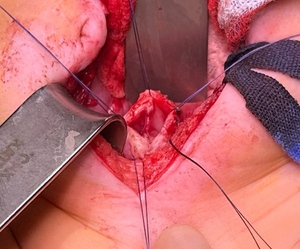

Once our patient reached 4 months old, the final surgery —a combined abdomino-perineal vaginal pull-through with septum resection— was performed by our department (figure 2). Following the procedure, a catheter was placed in the neovagina to prevent stenosis of the newly created vaginal canal and to ensure safe drainage of secretions. Antibiotic prophylaxis with cotrimoxazole was discontinued, and metronidazole along with cefotaxime was administered perioperatively. The catheter was removed after one week, with a follow-up scheduled to initiate regular neovaginal dilations. A new catheter was then reinserted and left in place for another week. Frequent follow-ups were performed with regular dilatation of the neovagina to avoid stenosis.